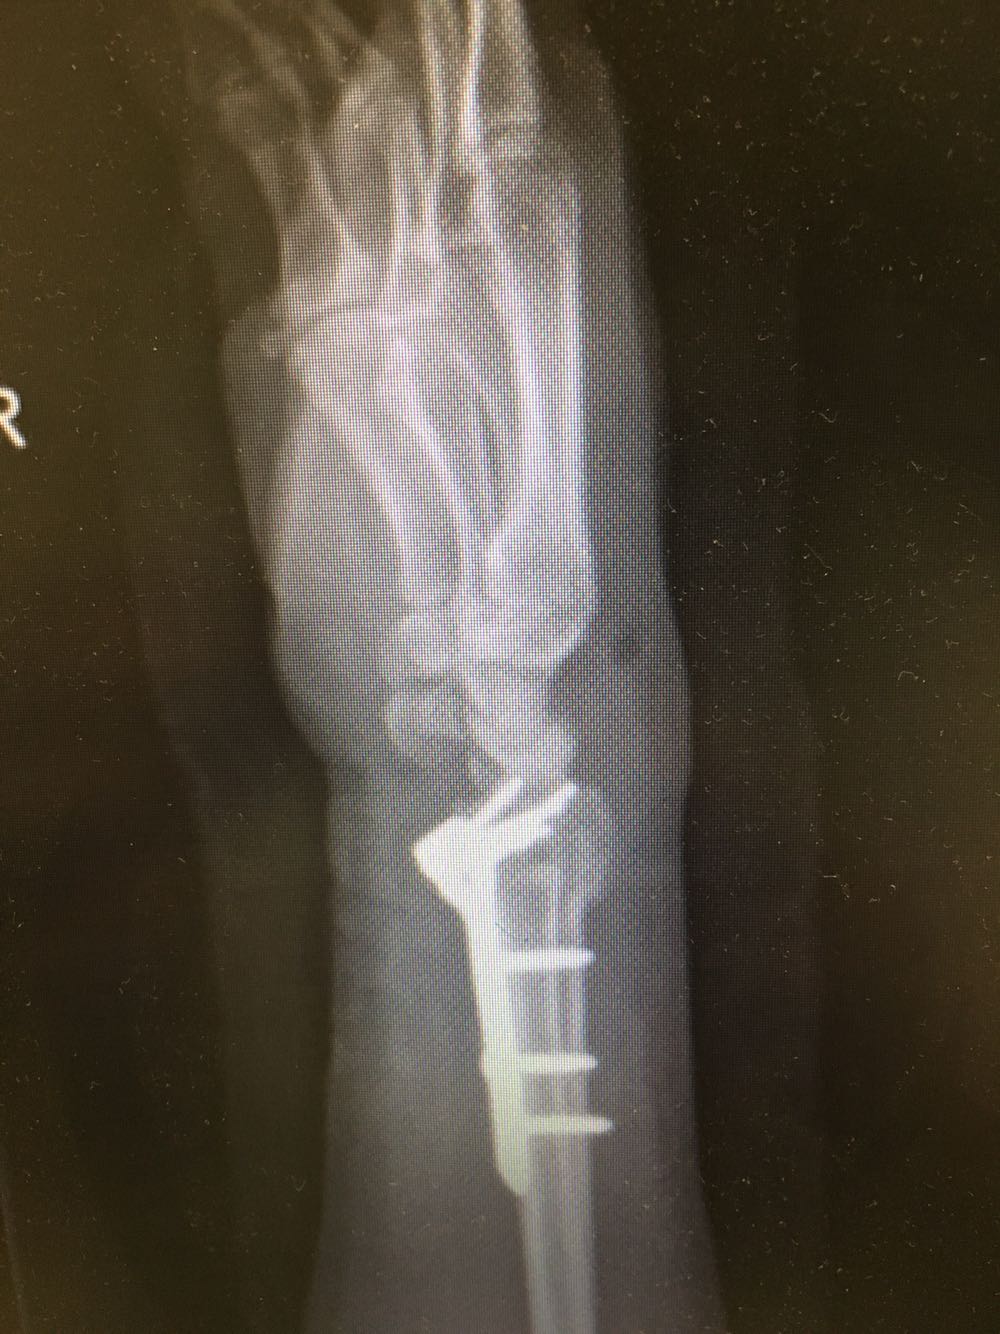

患者,女性,62岁 主诉:外伤致右腕部疼痛伴活动受限8小时 现病史:患者于8小时前受外伤后出现右侧腕部剧烈疼痛,后出现肿胀伴活动障碍,否认头晕头痛、恶心呕吐等不适,遂至我院就诊,查X片示:右侧尺桡骨远端骨折,现为进一步诊治收治入院,发病以来,神清,精神可,胃纳夜眠可,二便无殊,体重无明显变化。

查体:右侧腕部肿胀,压痛阳性,伴活动受限,远端肢体感觉及运动正常。 辅检:见现病史

诊断:右侧尺桡骨远端骨折 治疗:完善术前检查后行手术内固定